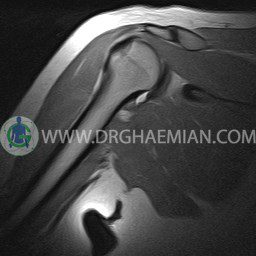

ام آر آی آتروفی عضلانی کتف بیمار

ام ار آی کتف یک روش تصویربرداری است که به وسیله آهنرباهای قدرتمند از قسمت کتف تصاویری ایجاد می کند. این نوع تصویربرداری از تشعشعات استفاده نمی کند. در این کیس آتروفی عضلانی کتف به همراه پارگی تاندون بالاخاری، بورسیت ساب دلتوئید و افیوژن مفصل دیده می شود.

– Complete tearing of supraspinatus tendon with grade 2 retraction and muscle atrophy

– AC joint hypertrophy with subacromial – subdeltoid bursitis

– Glenohumeral joint effusion

are seen.